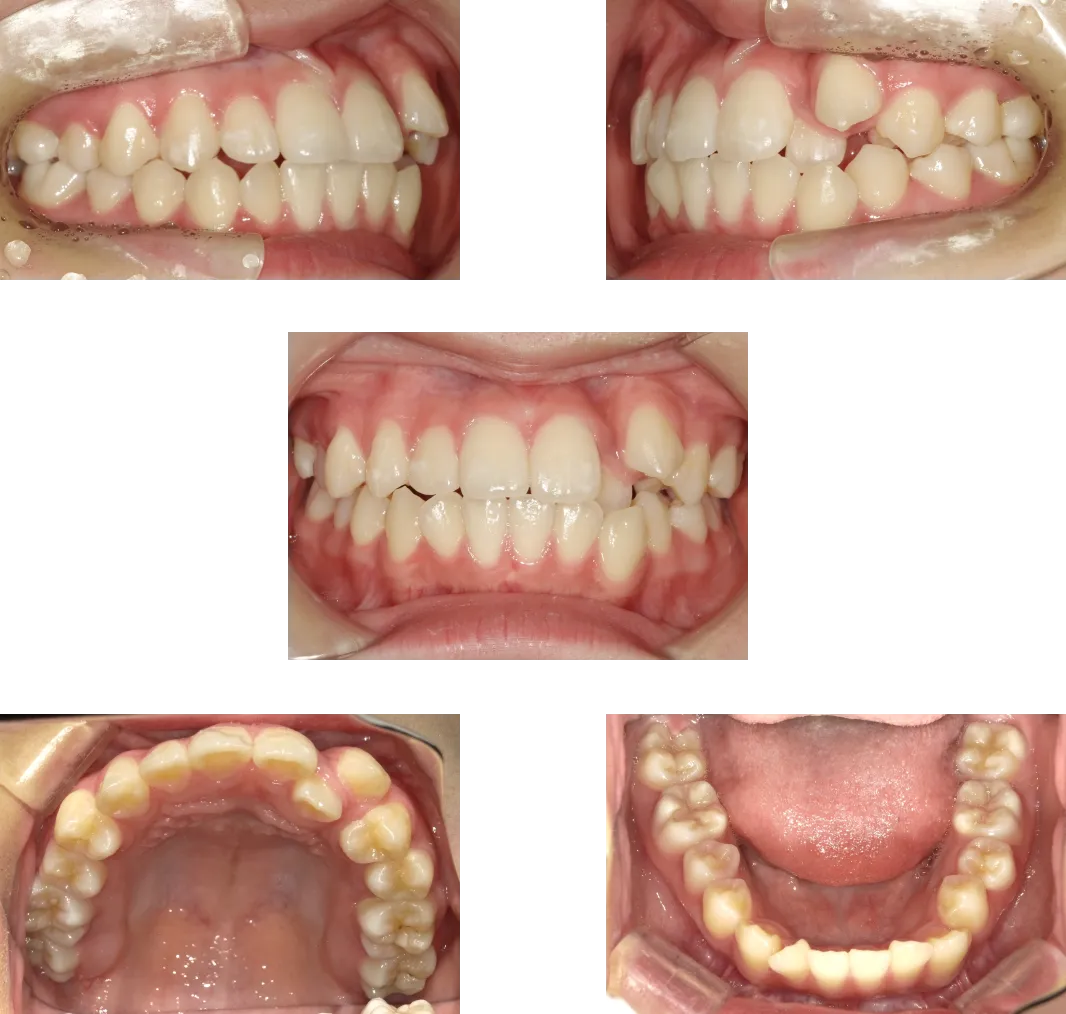

過蓋咬合 -20歳-

• Before

• After

診断

叢生、骨格性上顎前突

治療期間

1年6ヶ月+保定期間2年

料金

1,070,000円

抜歯

なし

リスク

痛み、軽度の歯根吸収、術後の変化